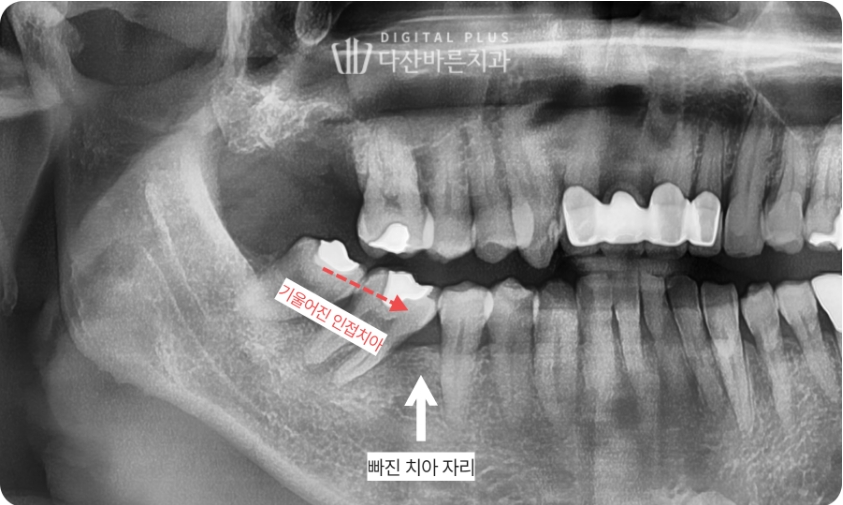

1. 인접치 이동 케이스

해당 환자분은 오른쪽 아래 어금니를 빠진 채로 방치하셔서

옆 인접 치아들이 빠진 치아 쪽으로 많이 기울어진 상태였는데요.

아래 파노라마 사진을 보면 치아가 기울어진 모습이 명확하게 확인됩니다.

▲ 초진 시 파노라마 사진. 빠진 치아 자리로 인접치들이 기울어진 모습.

이렇게 치아가 기울어지면,

기울어진 틈새로 음식물이 엄청 잘 끼기 때문에

상당히 불편합니다. 그리고 교합도 틀어지기 때문에

음식 씹을 때도 상당히 불편감이 느껴지실 겁니다.

빠진 치아 자리에 임플란트 치료가 필요하지만

이미 오랜 기간 인접치아들이 많이 기울어져,

임플란트 심을 공간조차 사라진 상태입니다.